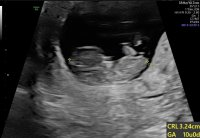

Så fine bilder!Må bare dele disse to bildene fra TUL som vi var på 1.DesemberLille knøttet lå å sprellet med føttene og hendene, og kosa med den ene hånda i fjeset sitt

Ah! Jeg skal på TUL når jeg er 11+3. Kjekt å vite at man får så fine bilder så tidligJeg trodde jeg var 10+0 på vei den 1.Desember, men jordmor som utførte TUL mente jeg var 10+3 grunnet størrelsen på babyen , så nå avventer vi til vi skal på OUL for å vite om vi får termin i slutten av juni eller starten av juli.

Mensentermin er 2.Juli men hvis det viser seg at jeg er 3 dager lengre på vei havner jeg vist på juni med termin![]()